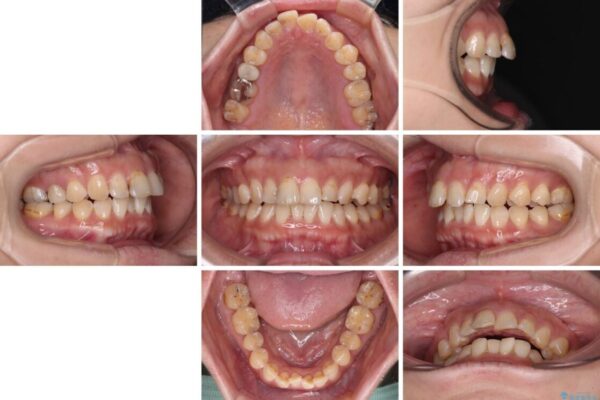

舌の突出癖が原因で上下の歯に大きなスペースが生じていたため、舌のトレーニングをしっかり行っていただくことで、上顎歯列をスムーズに移動させることができました。

治療後

• 【モニター】飛び出た前歯を整えたい ワイヤー矯正治療 治療後画像